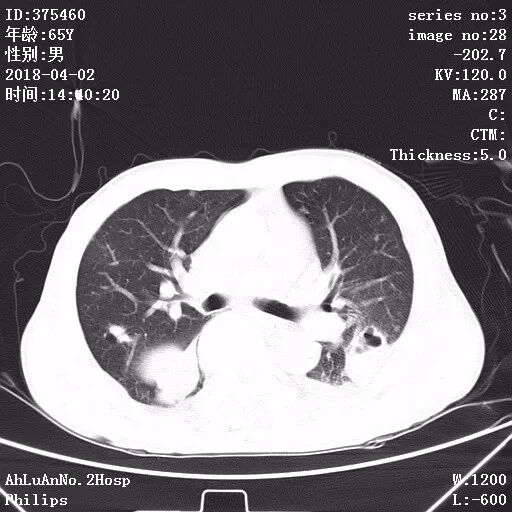

患者男,65岁,因“咳嗽、咳痰1月余,发热1周”入院。

两肺可见多发斑片状及气囊样阴影,部分气囊样影内可见气液平面,两侧胸膜腔可见少量液性密度影聚集。

结果:金黄色葡萄球菌肺炎

显示,白细胞计数和中性粒细胞百分比升高,可有核左移及中毒颗粒。本病的胸部X线特征常表现为肺段或肺叶实变,或呈小叶样浸润,其中有单个或多发的液气囊腔。

X线阴影的易变性是本病的另一重要特征,其常表现为一处炎性浸润消失而在另一处出现新的病灶,或很小的单一病灶发展为大片阴影。